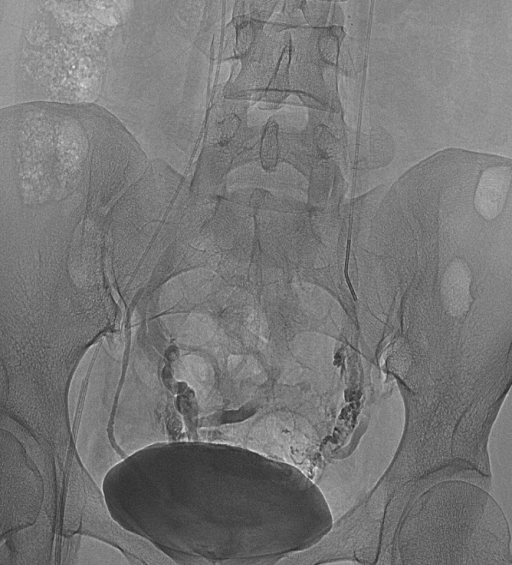

3.经皮导管逆行卵巢静脉造影术

目前认为是盆腔淤血综合征诊断金标准。

盆腔淤血综合征的介入治疗是在局部麻醉状态下,通过股静脉穿刺或颈静脉,引入导丝、导管,插入到盆腔静脉,进行盆腔静脉造影及予以硬化剂、金属弹簧圈等予以栓塞,将有病变扩张的盆腔静脉进行封闭,从而达到治疗的目的。